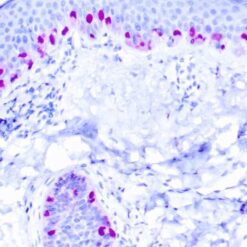

This antibody recognizes insoluble elastin, α-elastin, soluble non-cross linked precursor of elastin (tropoelastin). Elastin is an important polymeric protein of connective tissue that imparts elasticity to vertebrate elastic tissues.

| Clone | BA-4 |

| Immunogen | Bovine α-elastin |

| Positive Control Tissue | Heart, Kidney |